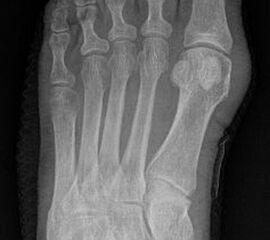

Röntgenmorphologische Einteilung nach Coughlin (I-III) ergänzt durch Fallat (IV) (Arnold 2002) 34

Typ I: Vergrößerter Metatarsale V Kopf

Typ II: Laterale Seitausbiegung des distalen Os metatarsale V

Typ III: Vergrößerter Intermetatarsalwinkel IV/V von mehr als 8°

Typ IV: Kombination von mindestens 2 Typen I-III

Abb. 2: Tailors bunion Typ I bis III (nach Coughlin)